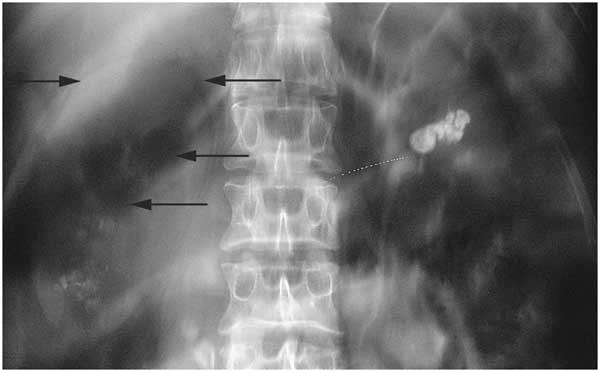

5. 신장결석

오른쪽 신장이나 요관에 결석이 생기면 극심한 옆구리 통증이 갑작스럽게 발생합니다. 통증은 파도처럼 심해졌다 약해졌다를 반복하며, 허리에서 옆구리, 아랫배와 사타구니 쪽으로 이동하는 양상을 보입니다. 혈뇨, 빈뇨, 배뇨 시 통증이 동반되는 경우가 많고, 진통제로도 쉽게 가라앉지 않는 것이 특징입니다.